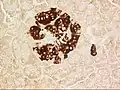

Mouse islet immunostained for pancreatic polypeptide

Mouse islet immunostained for insulin

Mouse islet immunostained for glucagon